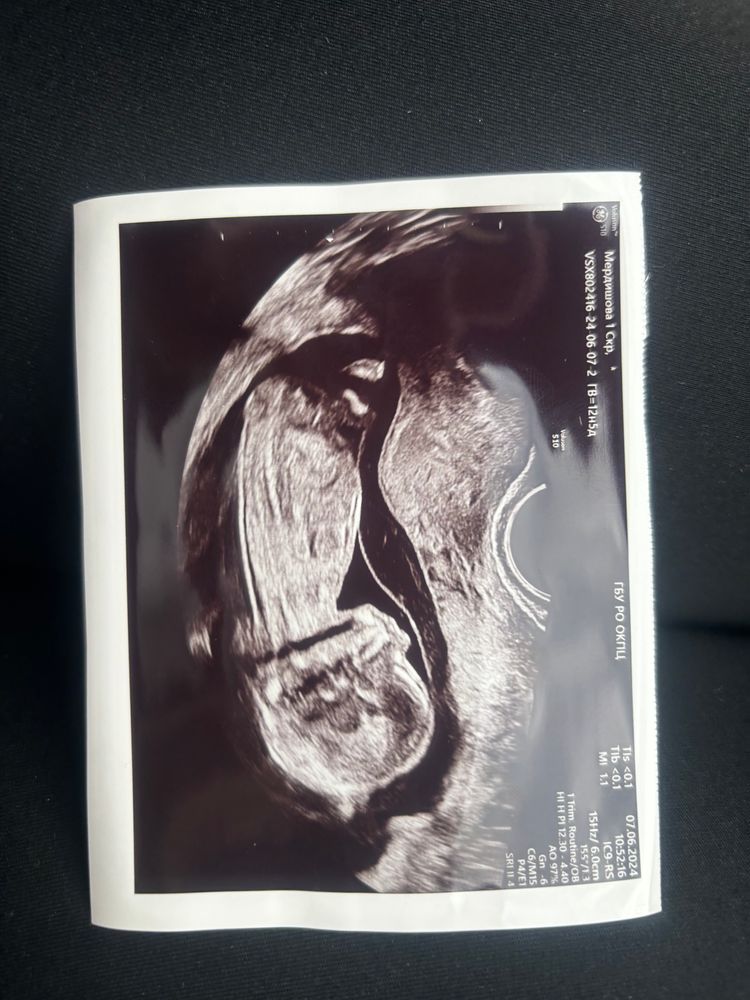

Изображение Вот мальчик

10.06.2022

Девочка

Да, похоже на девочку. Между ножек ничего не видно